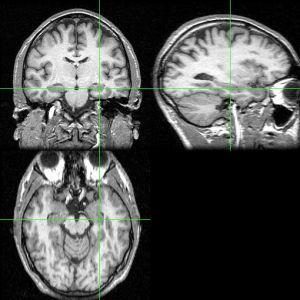

海马体(Hippocampus)又名海马回、海马区,是位于脑颞叶内的一个部位的名称,人有两个海马,分别位于左右脑半球。它是组成大脑边缘系统的一部分,担当着关于记忆以及空间定位的作用。名字来源于这个部位的弯曲形状貌似海马。 在阿兹海默病中,海马体是首先受到损伤的区域:表现症状为记忆力衰退以及方向知觉的丧失。大脑缺氧(缺氧症)以及脑炎等也可导致海马损伤。 在动物解剖中,海马体属于脑的演化过程中最古老的一部分。来源于旧皮质的海马体在灵长类以及海洋生物中的鲸类中尤为明显。虽然如此,与进化树上相对年轻的大脑皮层相比,灵长类动物尤其是人类的海马体在端脑中只占很小的比例。相对新皮质的发展,海马体的增长在灵长类动物中的重要作用是使得其脑容量显著增长。

许多人对海马区与癫痫发作的关系也有很浓厚的兴趣。海马区在脑中为发作阈值低的部位。因为几乎所有癫痫患者的发作皆由海马区所起始,像这类以海马区为主的发作,有许多的情形是很难以药物治疗的。而且,海马区中有一部分,尤其是内嗅皮质,为阿尔兹海默氏症最先产生病变的地方,海马区也显示出容易因贫血、缺氧状态而受伤害。